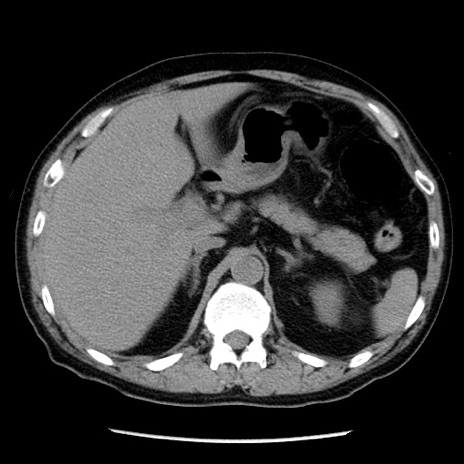

症例29(横断像)

【症例】40歳代男性

【現病歴】2日前から胃痛あり。徐々に周期的な激痛に変化した。本日になっても激痛があるため受診。

【身体所見】意識清明、BT 38-39℃台あり、腹部:膨満、やや硬、右下腹部に圧痛あり。

【データ】WBC 8500、CRP 23.26